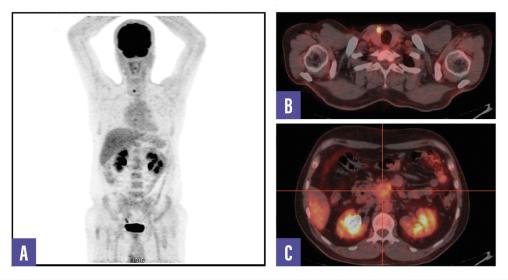

Un homme de 53 ans, sans antécédents, consulte pour des douleurs abdominales diffuses évoluant depuis plusieurs semaines. Le bilan biologique est normal. Une tomodensitométrie abdomino-pelvienne met en évidence une masse rétropéritonéale infiltrante associée à une adénopathie lombo-aortique. La tomographie par émission de positons (TEP-TDM au 18F-FDG) montre un hypermétabolisme léger de la lésion rétropéritonéale, mais l’adénopathie ne fixe pas le FDG (fig. 1). Un foyer hypermétabolique thyroïdien droit est également détecté. Une biopsie échoguidée confirme une tumeur neuro-endocrine digestive bien différenciée de grade 2 (Ki- 67 à 12 %). La scintigraphie au 99mTc-Tektrotyd révèle une fixation intense de l’adénopathie, compatible avec une pathologie neuro-endocrine exprimant les récepteurs de la somatostatine (fig. 2). Un nodule thyroïdien droit conduit à une thyroïdectomie totale, confirmant un microcarcinome papillaire.

L’association entre FRP et tumeur neuro-­endocrine (TNE) est exceptionnelle. Ce cas illustre une TNE bien différenciée, faiblement avide pour le FDG mais fixant intensément le 99mTc-Tektrotyd, combinée à un microcarcinome papillaire thyroïdien.